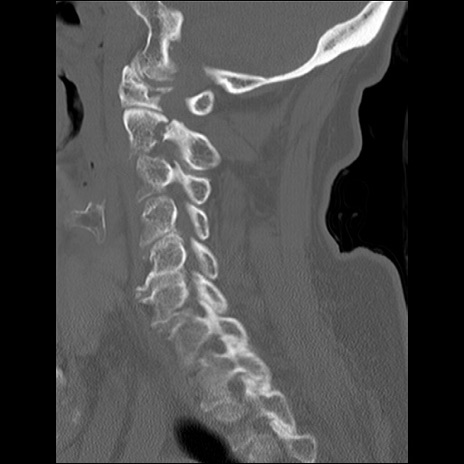

症例48 頚椎CT(矢状断像)

頚椎CT